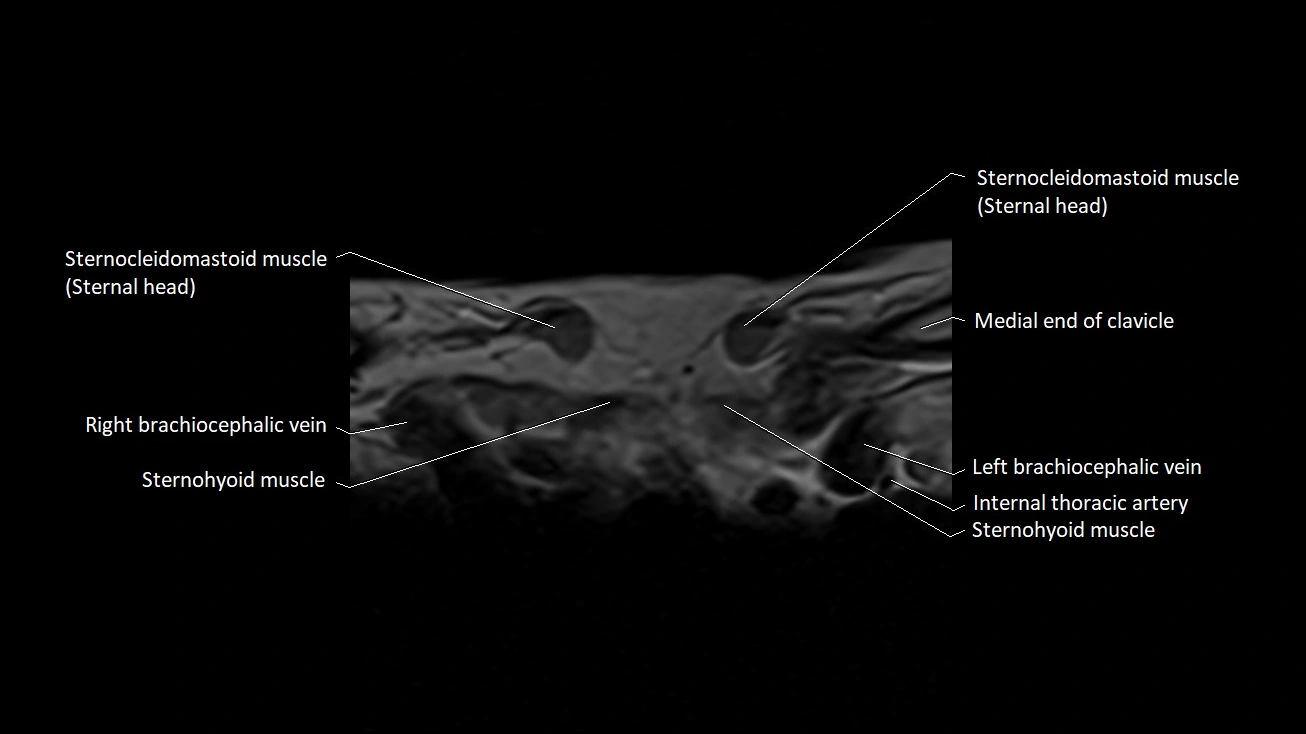

MRI images

image